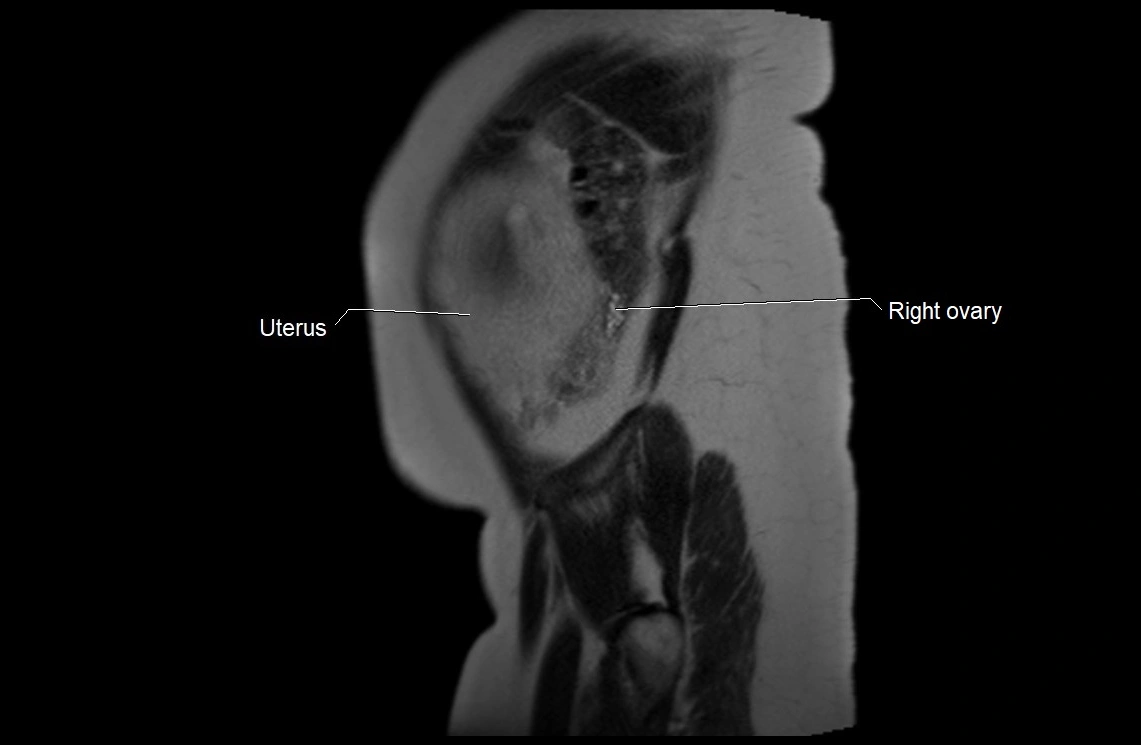

MRI image

image